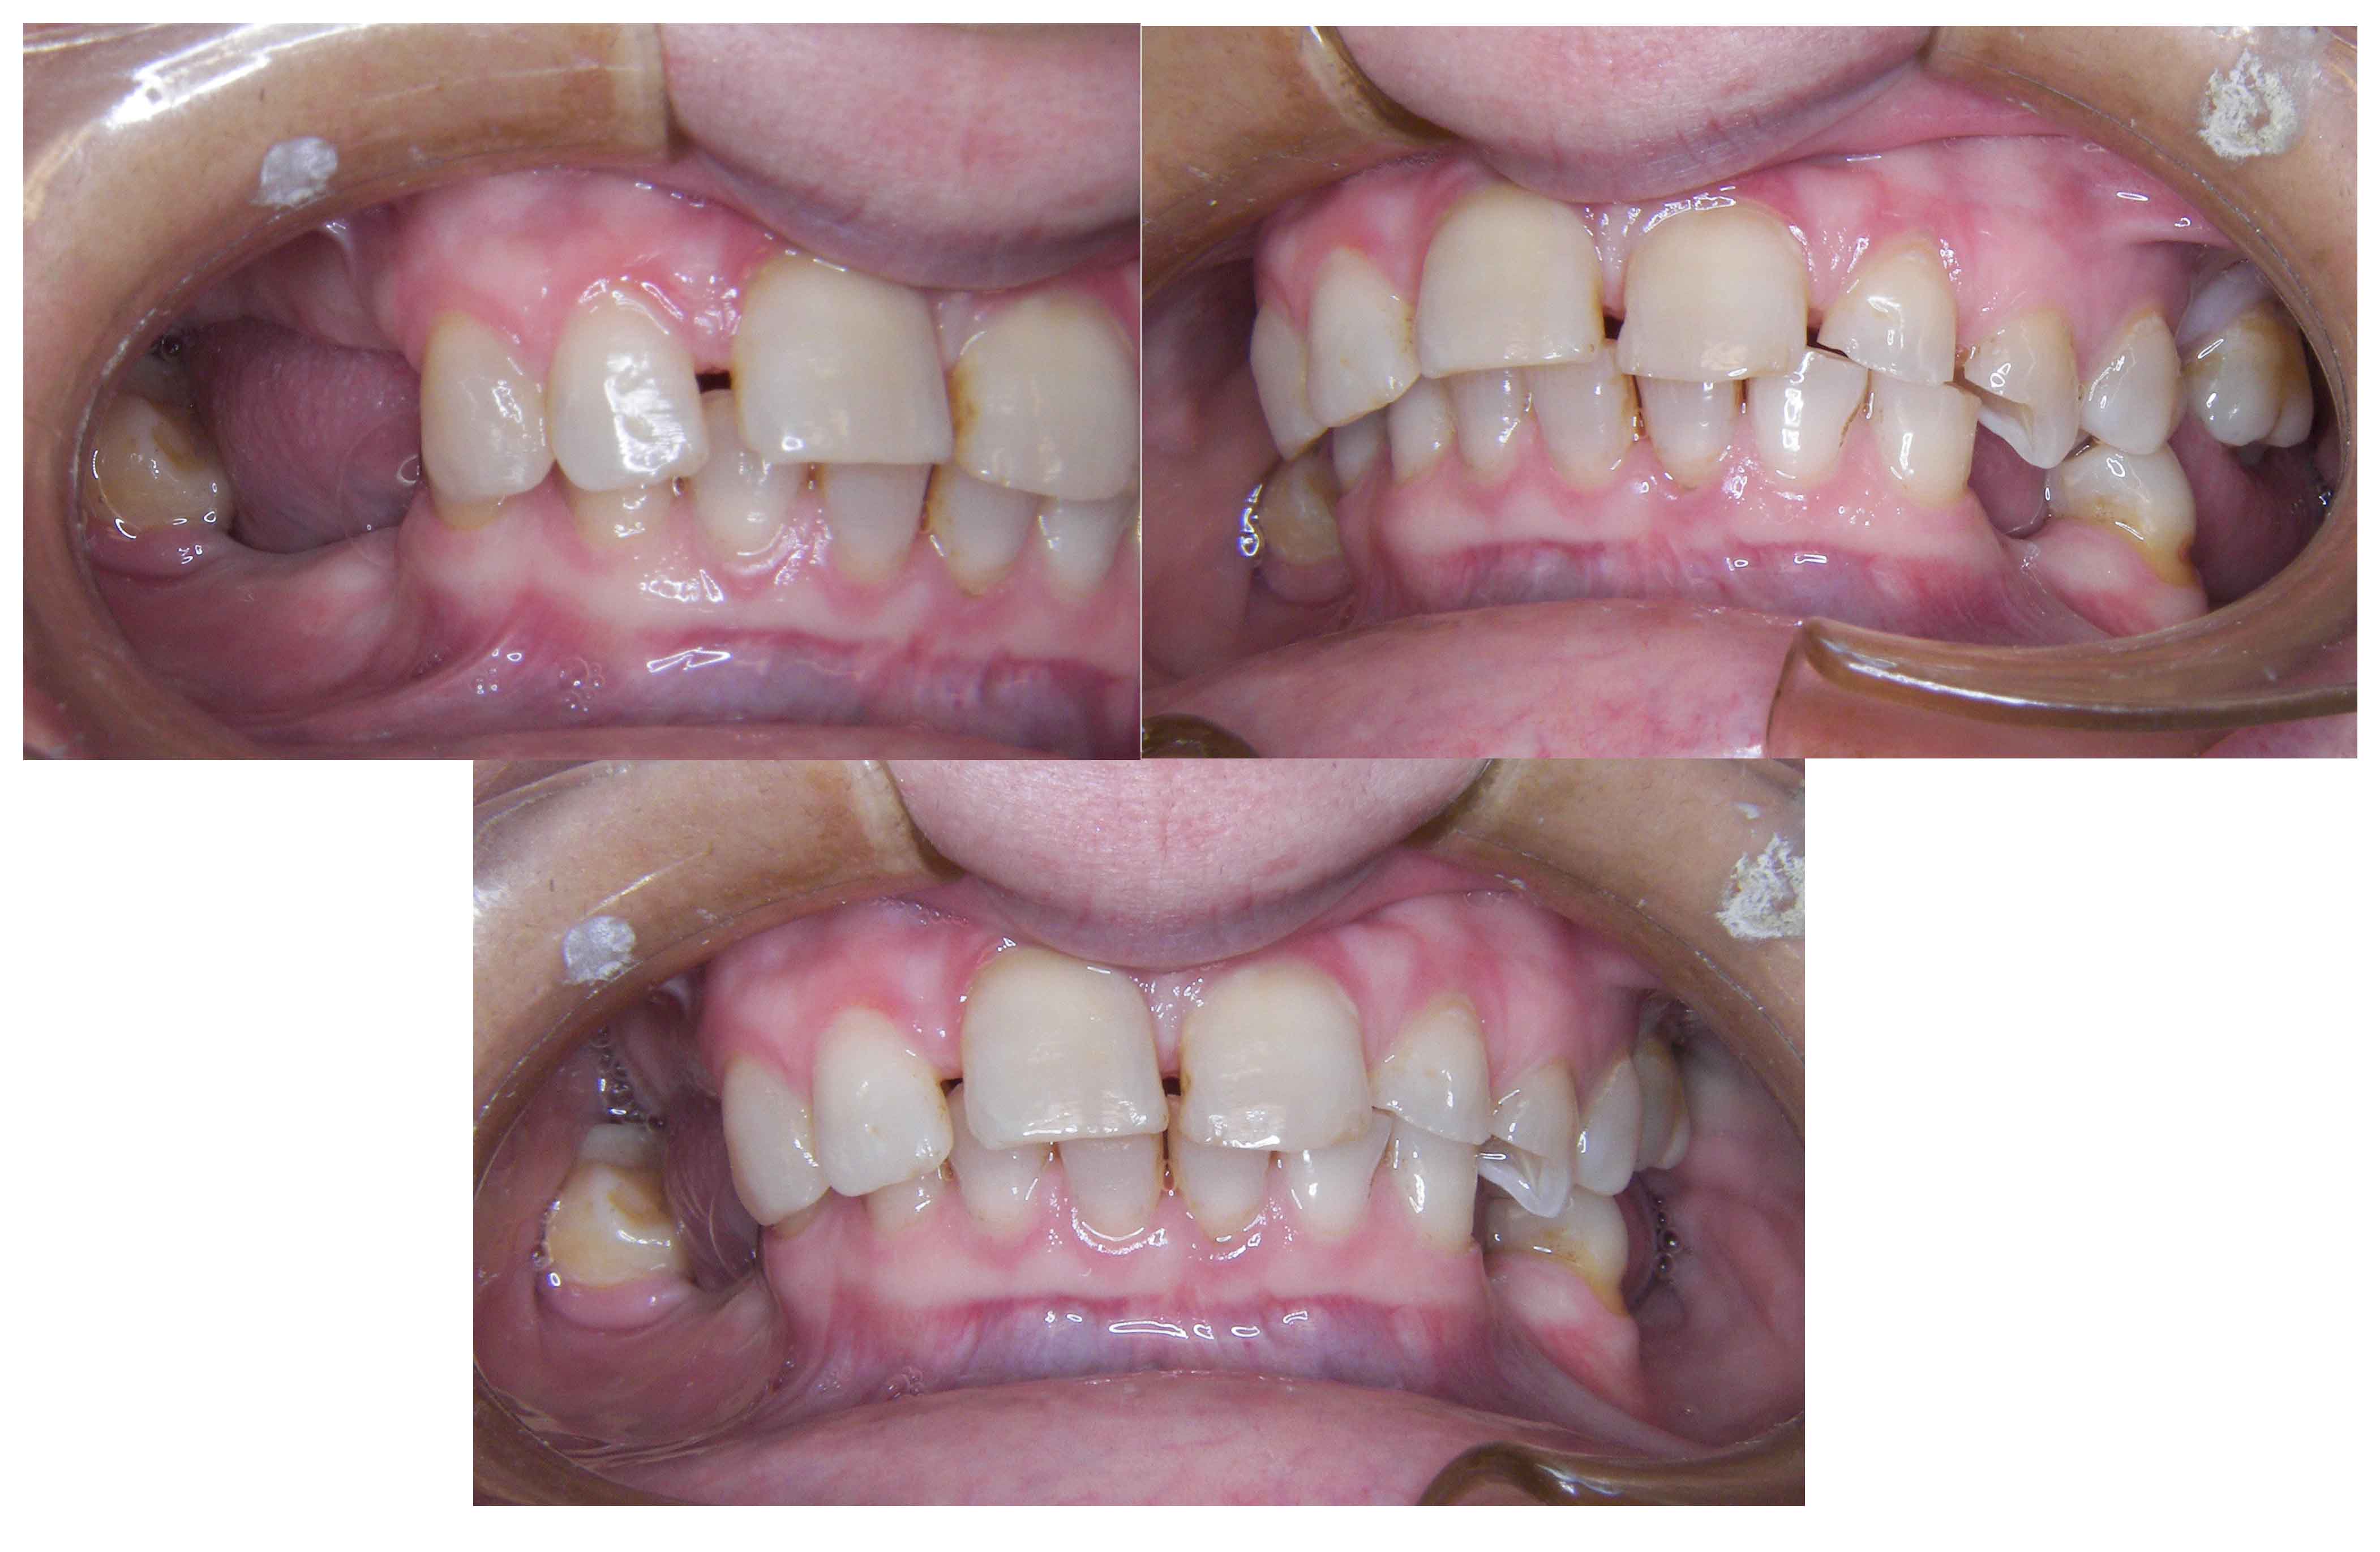

Tooth discoloration caused by tetracyclines

Aesthetic Rehabilitation with ceramic crowns and venners

Main problem:

Colour changes due to the use of tetracyclines as a child. Various treatments were done before to try to solve the problem but all of them were unsuccessful.

The Treatment:

Full crowns were opted to cover the teeth that were very damaged and venners were used to cover those who were less damaged and by doing this less natural tooth structure was damaged.